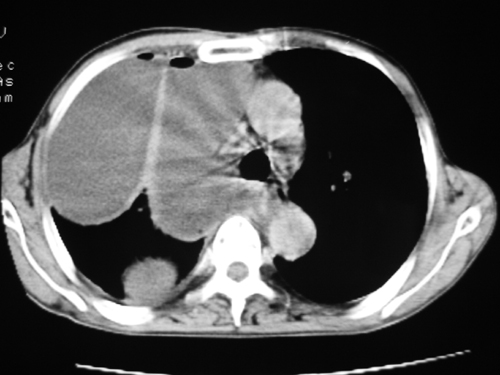

以下是引用zsl6918在2008-4-29 9:15:00的发言:[br]右侧包裹性积液穿刺术后改变,肺内多发结节不除外转移可能。建议查胸水,问病史。